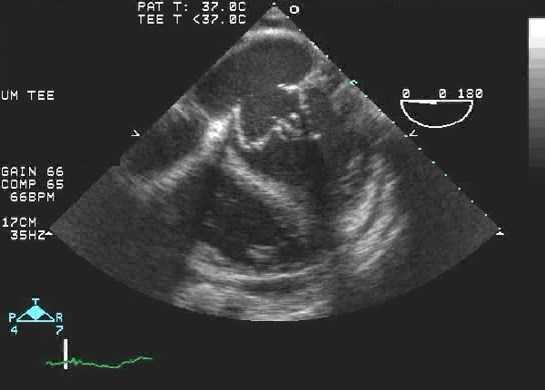

Обструкция протеза на эхокардиографии

Заболеваемость обструкции протезированных клапанов оценивается в 0,1% до 0,4% в год, в зависимости от размера клапана, его типа, расположения и адекватности антикоагуляции. Тогда как обструкция митрального механического протеза возникает чаще от тромба, причиной сужения механического протеза аортального клапана более часто является формирование паннуса. Когда работа протезированного клапана будет затруднена, происходит нарушение движения диска, шара, или уменьшается подвижность створки. Однако, это трудно выявить эти ситуации, и еще труднее оценить количественно, ограничение экскурсии на простой трансторакальной эхокардиографии. Чреспищеводная эхокардиография может в состоянии визуализировать нормальные и патологические движения протезированного клапана. Самый точный способ для выявления и количественной оценки степени обструкции протезов является допплер-эхокардиография. Допплеровское исследование должны быть выполнены датчиком с различных позиции, чтобы гарантировать, что фиксируется максимальная скорость в месте стриктуры протеза.

Тромб. Чаще встречается в механических клапанах и отвечает за многие случаи неисправности протеза. Это может произойти, если контроль антикоагуляции плохой или при наличии расширенных камерах сердца. Антикоагуляция необходима для всех механических клапанов (стремитесь к международному нормализованному отношению [МНО] 3,5-5,0). Восприимчивость протезов клапанов к тромбозу зависит от их положения (связанного с градиентом давления на клапане). Иногда пациенты жалуются, что больше не слышат щелчки клапана — это может быть признаком тромбоза.

ЭхоКГ может обнаружить тромб с помощью:

- Визуализации подвижного образования на клапане - ее бывает сложно отличить от вегетаций или кальцинированных узелков

- Уменьшение или отсутствие движения подвижной части клапана (например, шара, диска, створок)

- Сопутствующее расширение камер сердца.

- Как и в случае с вегетациями, в M-режиме может отображаться несколько темных эхо-линий и / или уменьшенное открытие или закрытие клапана. Допплерография и ЦДК могут указывать на препятствие для открытия клапана (повышенная скорость потока) или препятствие для закрытия (новая чресклапанная регургитация или увеличение степени тяжести существующей регургитации).